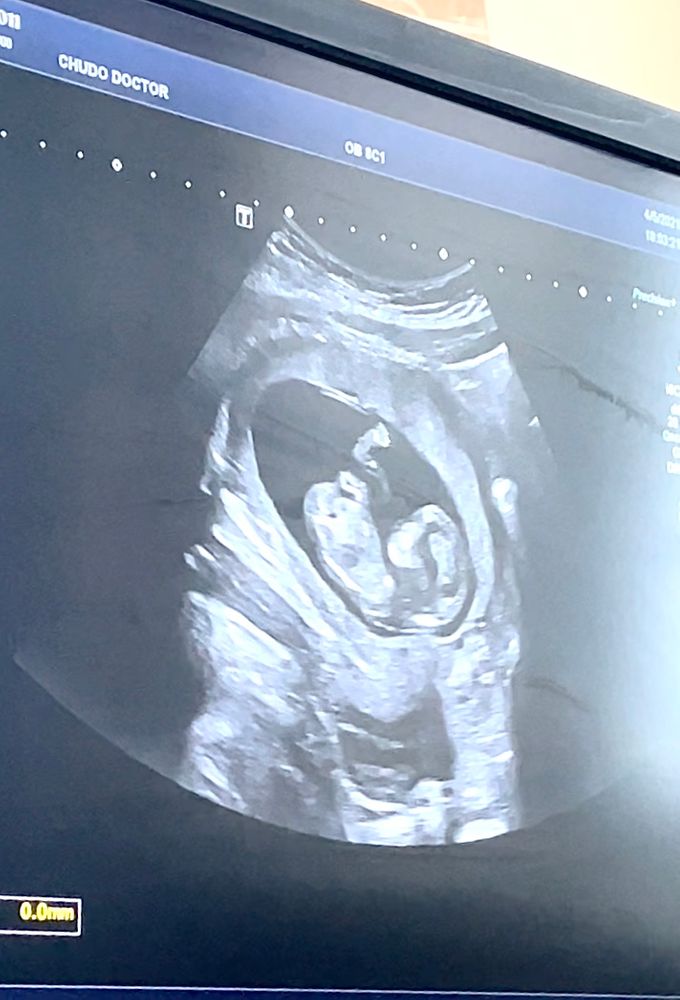

Первый скрининг 🤰🏽

Срок по УЗИ 12+6, по М 11+6

Так прикольно, даже пятки было видно и ясно, что нос, как отца, глубоко посажен👏🏽

ПЯ 59 мм (13 нед.)

КТР 64 (12+6 нед.)

БПР 21,1 (13+3 нед.)

ЛЗР 28 мм (12+1 нед.)

Носовые косточки лоцируются нечетко 4,6-4,7 мм

ТВП 2.0 мм

ЧСС 158 уд/мин

Плацента 18 мм, на правой заднем-боковой стенки матки, 0 ст. зрелости.

Длина шейки 31 мм. Зев сомкнут, цервикальный канал не расширен.

Двигательная активность удовлетворительная